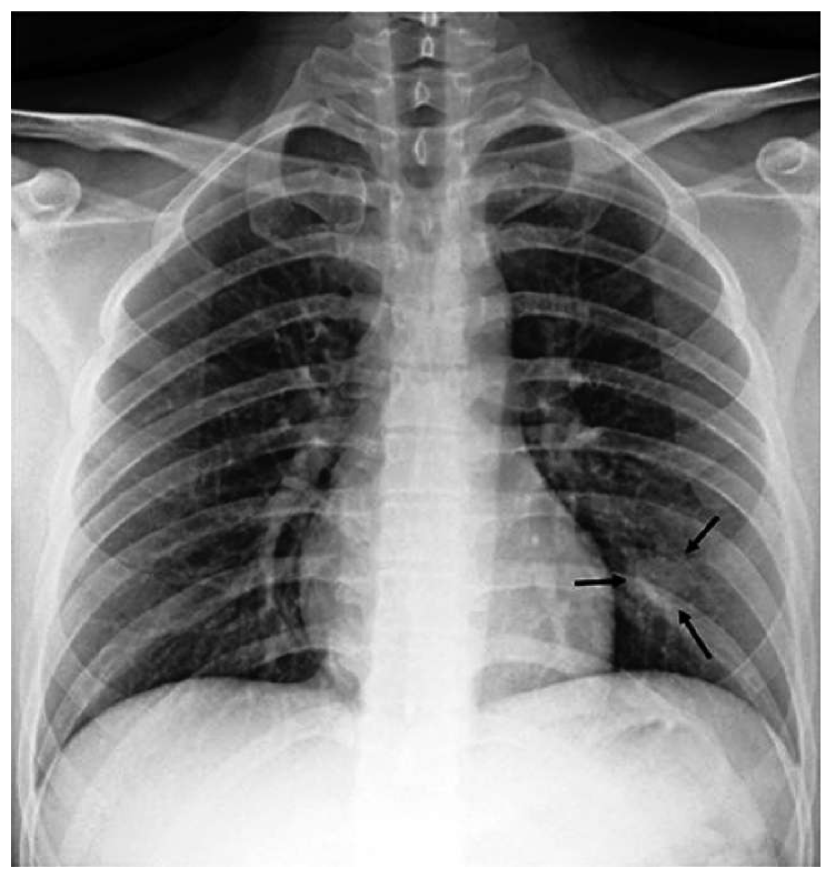

As an extra step, we expanded COVID-CXNet for multiclass classification between normal, COVID-19 pneumonia (CP), and non-COVID pneumonia to examine its performance regarding the differentiation between two types of pneumonia. CP is often appeared with bilateral findings, whereas non-COVID pneumonia or CAP mostly has unilateral consolidations. Since most images are collected from the CXR-14 dataset, a histogram matching is applied to adjust histograms according to a base image. The output layer is changed to have three neurons with the SoftMax activation function. Confusion matrix is shown in Table 4.

Accuracy score is 81.04%, with f-scores of 0.85 and 0.76 for CP and CAP classes, respectively. In a number of cases, especially in the first stages of virus progression, CP has unilateral findings. Also, CAP may cause bilateral consolidations. Therefore, some cases are expected to be misclassified between CP and CAP. From the confusion matrix, it could be seen that a relatively high number of images are misclassified between CAP and normal. A potential reason for this issue is considered to be related to wrong labeling. Besides, some CAP CXRs are from patients with early-stage disease development. To confirm the model performance, Grad-CAMs are plotted in Fig. 19.

Refer to caption

Figure 19: COVID-CXNet multiclass classification visualization results

The model is properly looking at one lobe for detecting CAP and both lobes for CAP and normal images. There are some wrong labels, nevertheless. A figure containing more visualizations is found in Appendix C. To further enhance statistical scores, a hierarchical approach is implemented. In the first level, we classify images into normal and pneumonia classes. In the second level, pneumonia images are categorized into CP and CAP. Final confusion matrix is illustrated in Table 5.